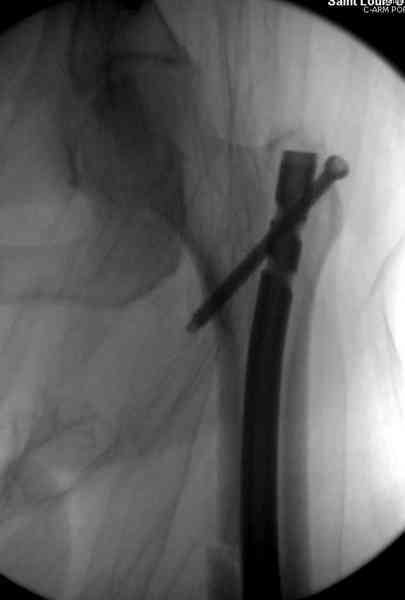

Здесь представлены снимки больного 65 лет, поступившего с диагнозом перелом

бедра после автоаварии.

В первый же день произведено антеградное штифтованием DePuy Trochanteric Nail.

На второй день (7) обнаружен пропущенный перелом,

сделаны Компьютерная Томограмма

и проведены шурурпы через и спереди штифта без удаления.